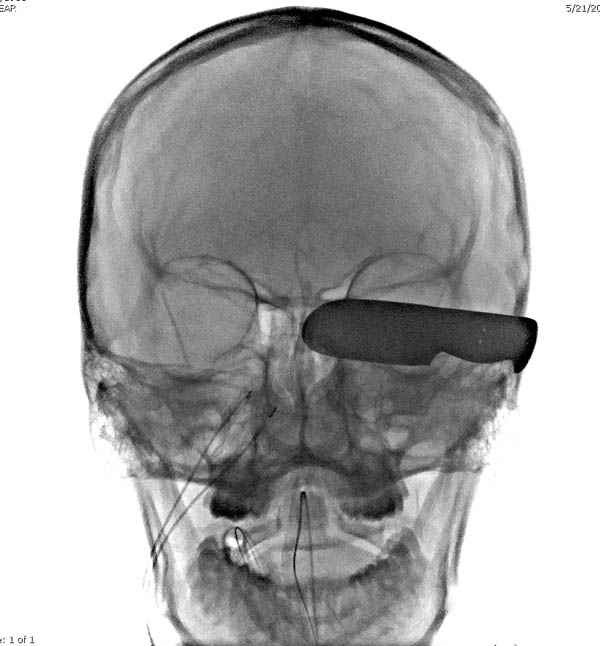

В своих выступлениях я рассказывал, что наши центры в мирное время по пенетрирующим травмам не уступает Ираку или Афганстану, и вот недавно к нам поступила больная 22 лет, травма "ножом в глаз" от бывшей подруги нынешнего "бой френда".

При поступлении в сознании, жаловалась на неприятные ощущения в глазнице.

По протоколу сделаны все необходимые исследования: рентген, ангиограмма с 3Д реконструкцией, где обнаружили что все жизненно важные сосуды не задеты, даже некоторые "сидят" изгибаясь на ноже.